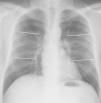

Finalmente, un tercer sistema de cuantificación (8) divide ambos pulmones en 8 campos pulmonares, según queda reflejado en la figura 2. La afectación de 1-3 campos implica un grado leve; moderado cuando 4-6 campos están involucrados, y grave si hay 7 u 8 campos afectados.

Radiografía de tórax posteroanterior que muestra la división en 8 campos pulmonares mediante tres líneas horizontales (sistema de cuantificación 8). Campo pulmonar superior (de vértices al borde superior del botón aórtico), campo pulmonar medio hiliar (desde botón aórtico a hilios), campo pulmonar medio paracardíaco (desde hilios hasta tercio inferior de la silueta cardíaca), campo pulmonar inferior (desde tercio inferior de silueta cardíaca hasta senos costofrénicos).